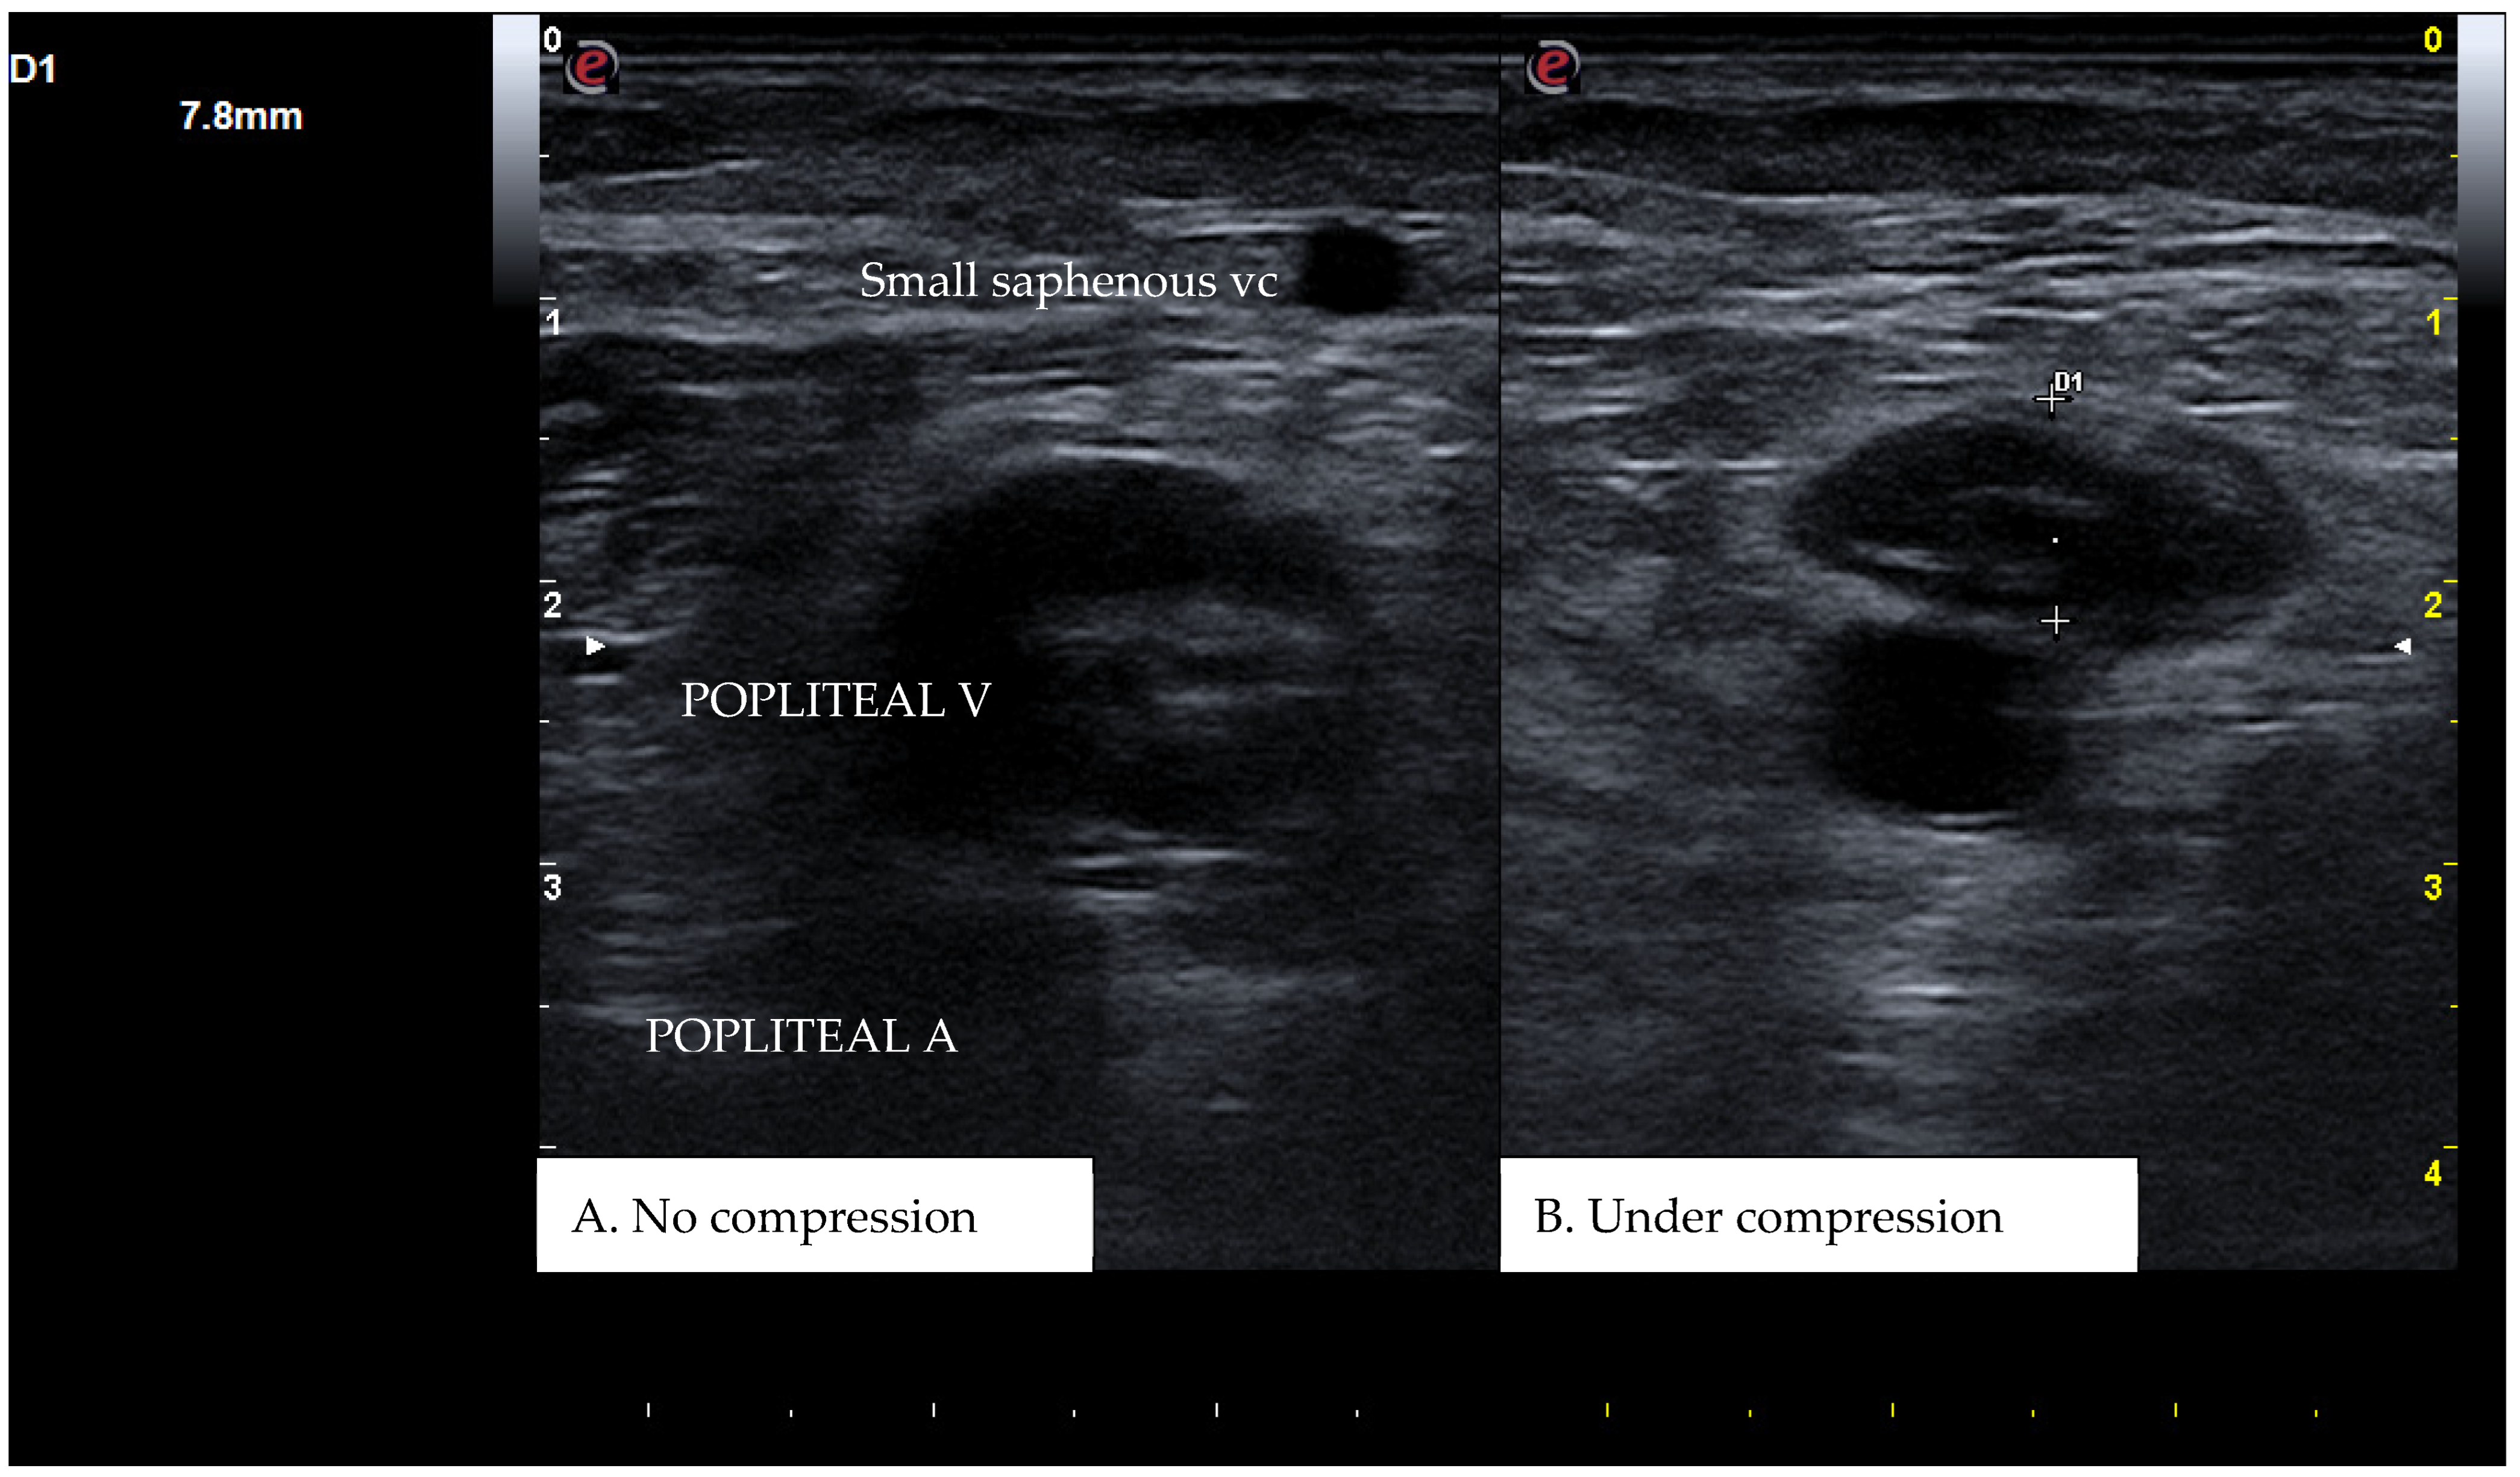

CUS is a diagnostic technique primarily designed to find DVT by checking the veins’ compressibility with the principle that healthy veins are normally compressible and would collapse under the pressure of the ultrasonographic probe. In the case of the presence of a venous thrombus, the vessel would not be able to collapse under such pressure [8,9]. Linear high-frequency transducers are generally used for CUS as they best visualize leg veins [10]. The ultrasound machine settings must be adjusted carefully in order to limit possible operator-related bias. Important elements to be considered in this setting include gain, focus, and time-gain compensation. Gain adjustment regulates image brightness, focus optimization sharpens the image to the desired depth, and time-gain compensation enhances the visibility of subtle echoes, ensuring uniform image quality [10,11]. The transducer partially compresses the vein, which creates an echogenic response. In normal veins, this technique should fully compress the lumen [9]. However, with thrombosis present, the vein does not collapse enough, which causes a non-continuous echogenic line [12]. While the femoral veins are usually well identified in the groin and thigh areas, to facilitate better visibility of the popliteal veins, the patient may lie in a supine position with the leg slightly abducted to relax the muscles or, alternatively, in a prone position [9]. Real-time B-mode and Doppler imaging are both valuable tools in this process. B-mode imaging can find incomplete vein collapse during compression [13,14]. Doppler imaging can show the thrombus or find a complete lack of flow in the lumen [9]. As such, CUS for DVT diagnosis involves evaluating direct signs like the presence of a non-compressible echogenic line suggesting a thrombus, as well as indirect signs like changes in vein compressibility and thrombus echogenicity [6,7]. In addition, evaluation of flow patterns and flow response during augmentation maneuvers may refine the diagnostic examination, although their implementation requires more advanced training and skills than simple CUS [7]. Clinicians should assess a spectrum of veins, including the external iliac, common femoral, superficial and deep femoral, popliteal, tibial, peroneal, gastrocnemial, and soleal veins, as well as the junctions with the great and small saphenous veins, representing the superficial systems [15]. Challenges exist in visualizing the iliac veins, especially in obese patients, yet phasic flow in the femoral veins can be indicative of DVT status, particularly for excluding iliac vein thromboses [16]. This comprehensive approach is standard in differentiating healthy veins, which should collapse and enlarge with augmentation maneuvers, from those with thrombosis, which show impaired response to pressure and flow changes [12,17]. Figure 1, Figure 2, Figure 3 and Figure 4 show real examples of DVT affecting different sites of the lower limb deep venous system, diagnosed through a CUS modality.

Figure 2. A real example of popliteal vein thrombosis at the level of the left popliteal cavity. D1 shows the residual diameter of the non-compressible vein (i.e., the maximum diameter of the relative venous thrombus).